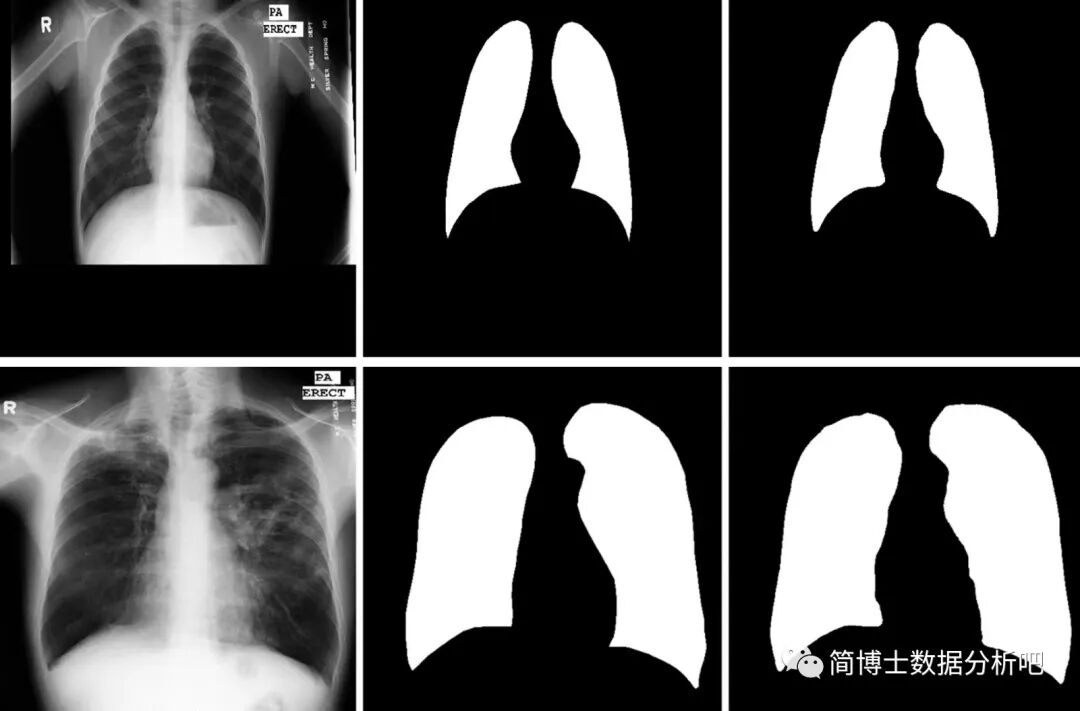

「深度学习」:在进行医学影像识别分析中的应用相当广泛